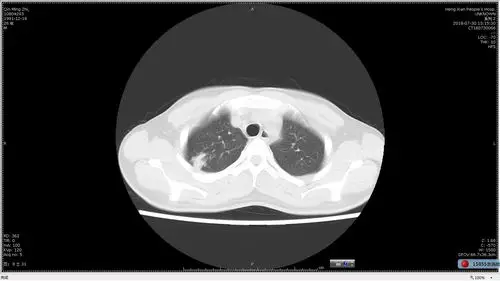

从ct上判断肺结核传染性的三种征象

胸部ct双肺继发性肺结核,右上肺空洞形成.